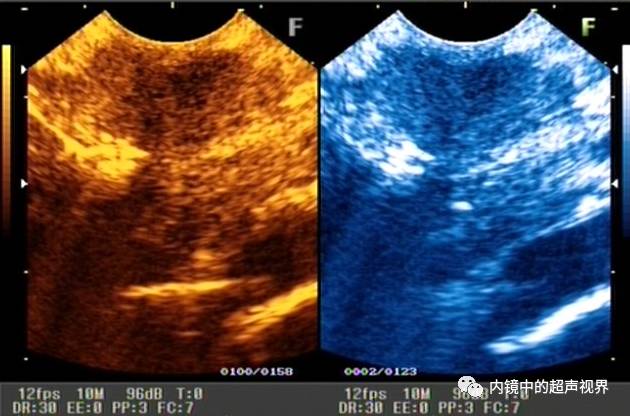

再来一张间质瘤的图片,也是DR30和80的对比。

有没人觉得,这个间质瘤的图片跟前面两个病灶不太一样,似乎感觉高DR模式看起来更舒服,那是因为,间质瘤为低回声,它周围的软组织为高回声,本身就能形成良好的对比,无需降低DR,而高DR模式更显细腻。

间质瘤